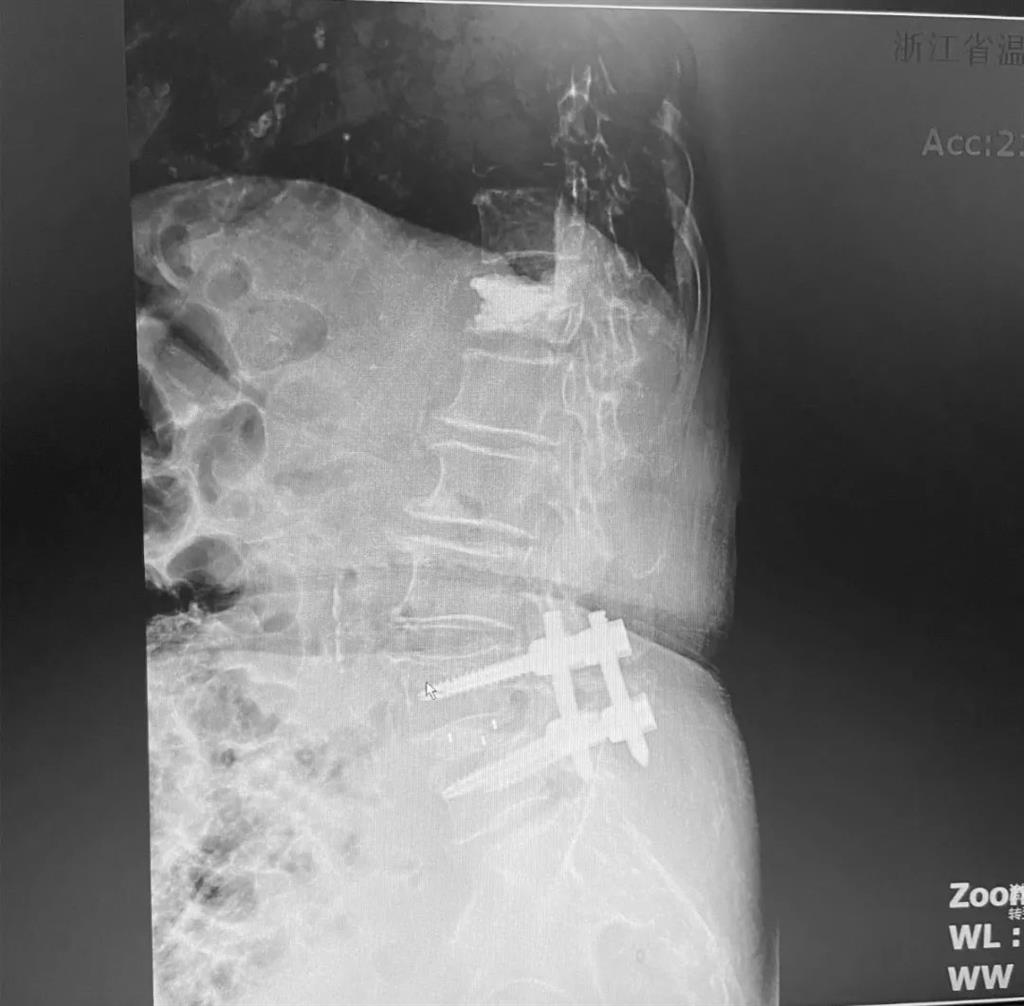

據(jù)了解,脊柱內(nèi)鏡下腰椎融合術(shù)只需要打幾個(gè)“鑰匙孔”即可完成。聽起來是不是很簡單?在脊柱內(nèi)鏡下,劉丹主任先后為患者進(jìn)行了椎管減壓、椎間盤摘除,再實(shí)施椎弓根螺釘放置、椎體植骨融合內(nèi)固定,一系列步驟有條不紊。

術(shù)中只需切開4個(gè)如“鑰匙孔”般大小的孔道